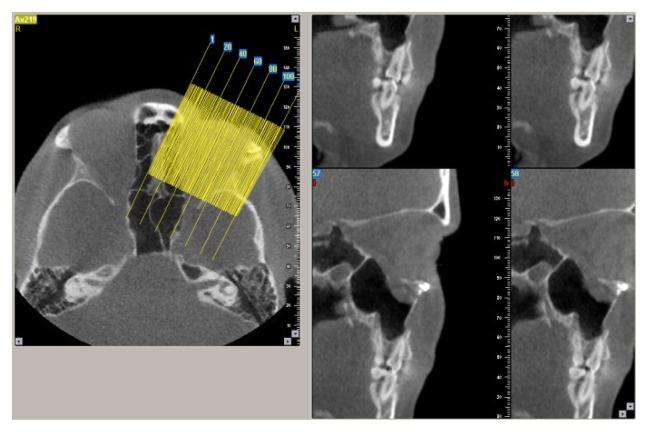

CBCT examination of the mid-face fractures area involving the floor of the orbit was performed in a number of 93 trauma patients by two independent radiologists. Both radiologists assessed the axial, coronal and sagittal sections and also the oblique coronal and sagittal extracted sections evaluating the location of the orbital fractures, its size and displacement, the involvement of the infra-orbital foramen, herniation of fat or muscle within the maxillary sinus, the overall type of the fracture and the implication of lateral or medial orbital wall. We also registered the section that provided better confidence of both examiners in visualizing the fracture of the orbit floor and the presence of herniated soft tissue, on different reformatted sectioning.

The presence of pure fracture of the orbital floor was detected in 11% of patients. The association of the orbital fractures with the zygomatic fractures was identified in the majority of the patients. In 86% of patients the displacement of the floor of the orbit was visualized, and in almost 30% of cases more than 50% of the orbital floor was involved in the fracture. Regarding the confidence between examiners, they were more confident using the oblique sagittal CBCT reformatted images for fracture detection and bone displacement evaluation, as for the soft tissue herniation the oblique coronal sections provided the highest level of confidence.

Mid-face trauma involves the orbital floor in the majority of situations. CBCT allows to obtain oblique images extracted from the three dimensional (3D) data that provide high confidence level in assessing pure orbital floor fractures.